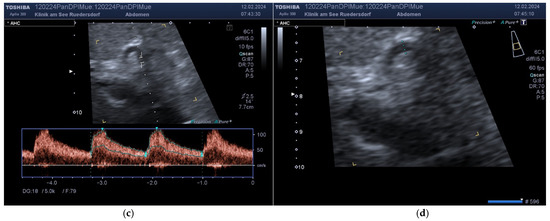

2.3.2. Location of the Probe, Insonation Angle, and Doppler Window